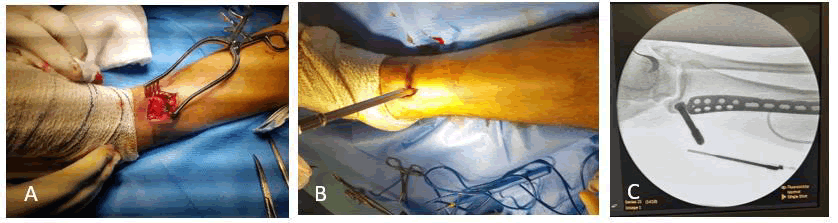

Patients in the supine position, draping done, 4-5 cm incisions proximal and distal far away from fracture site (without disrupting the fracture milieu). The locked plate was inserted in the submuscular plane after fracture reduction and external manipulation to gain rather anatomical alignment than anatomical reduction under fluoroscopy imaging; the anatomical plates were introduced from its straight (non-anatomical arm; for easy insertion with minimal fracture fragments’ disruption). Usually, the first screw(s)on either side of the fracture were nonlocked to achieve a reduction in a way that made the plate in close contact with the bone. Then the rest locked screws tightened in place, leaving the fracture area not fixed nor penetrated even with an inter fragmentary screw. Formal closure in layers, skin closed with stapler (Figures 1 and 2).

Fig. 1. Presents some operative steps; A) Preparing the tunnel for plate insertion. B) Insertion of the anatomical locked plate with the aid of a sleeve tightened to the most distal plate hole. C) Fluoroscopy checking image for proper plate insertion and bone alignment.